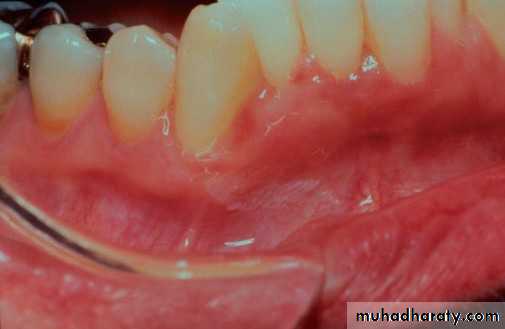

• • Lichen Planus (reticular)

• • Slightly elevated lines “wickham’s striae”

• Buccal mucosa

• Lichen planus (papular & reticular)